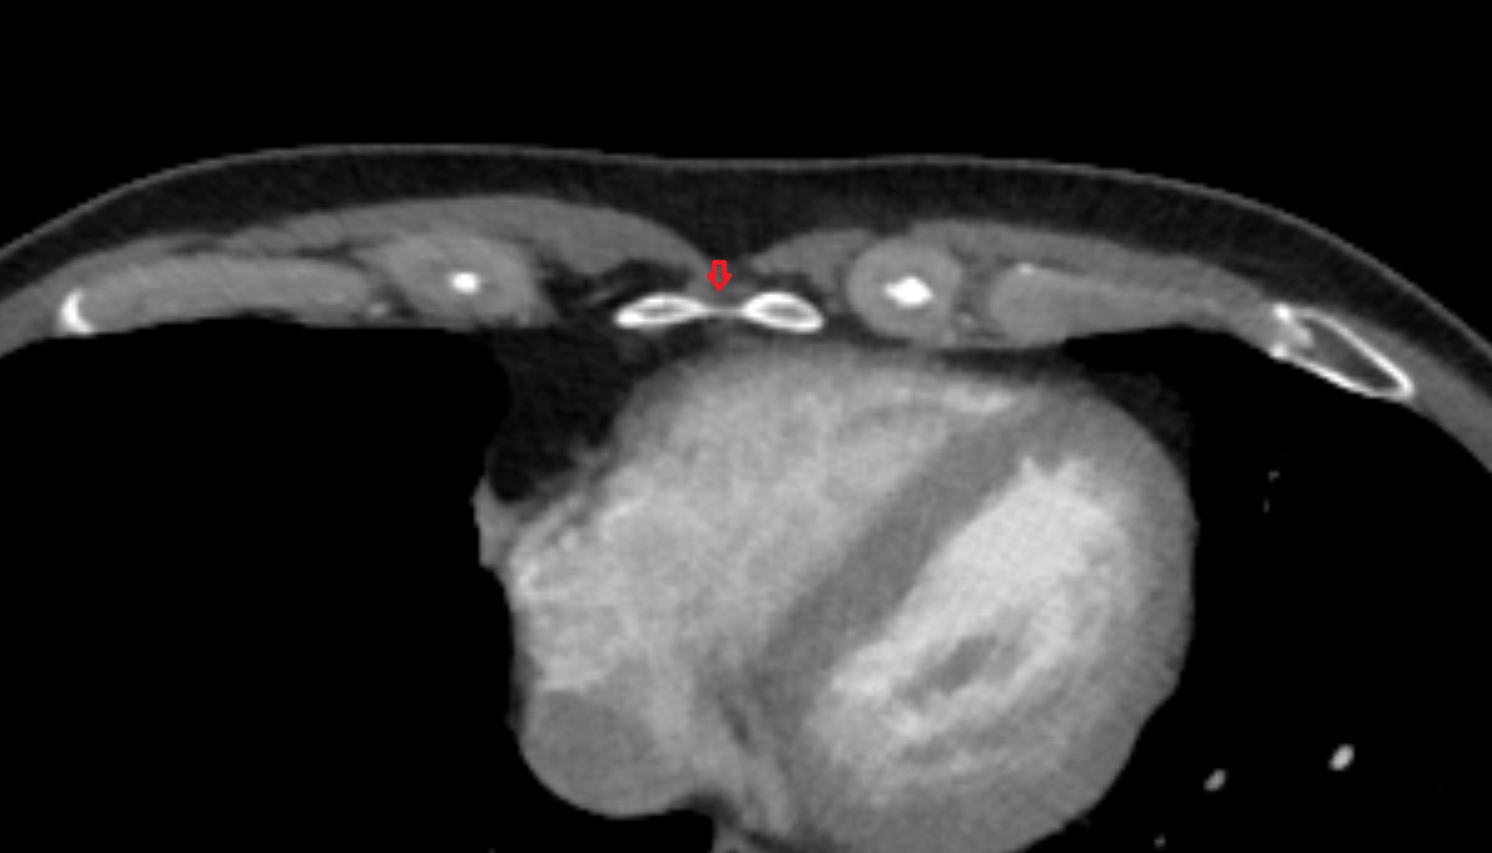

- Corpus cavernosum

- Corpus spongiosum

- Bulb of Penis

- Crus of penis